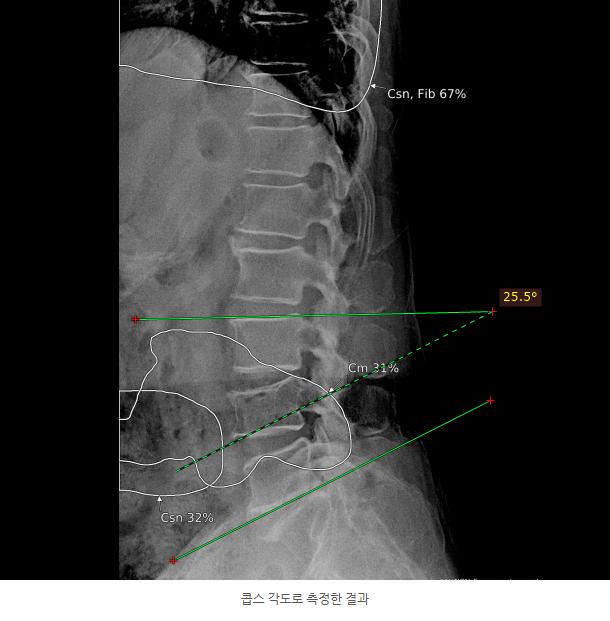

3.jpg 이미지

산재 보험의 압박률 측정방법과 압박률에 따른 산재 장해 급수는 위와 같습니다.

2018년 이후 가입한 보험의 경우 cobb's 각도에 의하여 각변형을 측정하게 됩니다.